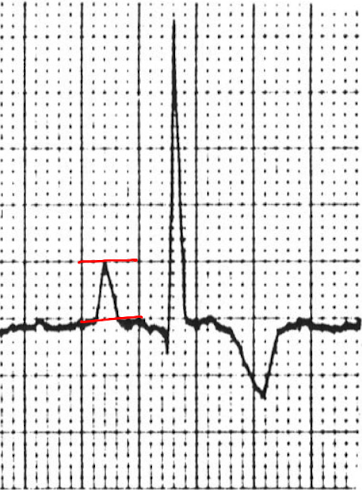

what is the length of the P wave

A

0.08s

whats the height of the P wave

0.5 mV

because 1 box = 0.5 cm and 1 cm = 1 mV